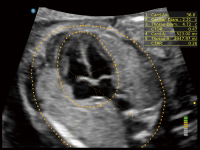

高清無損放大下的NT自動(dòng)測(cè)量

S-Fetus? 鳳眼(A4C切面)